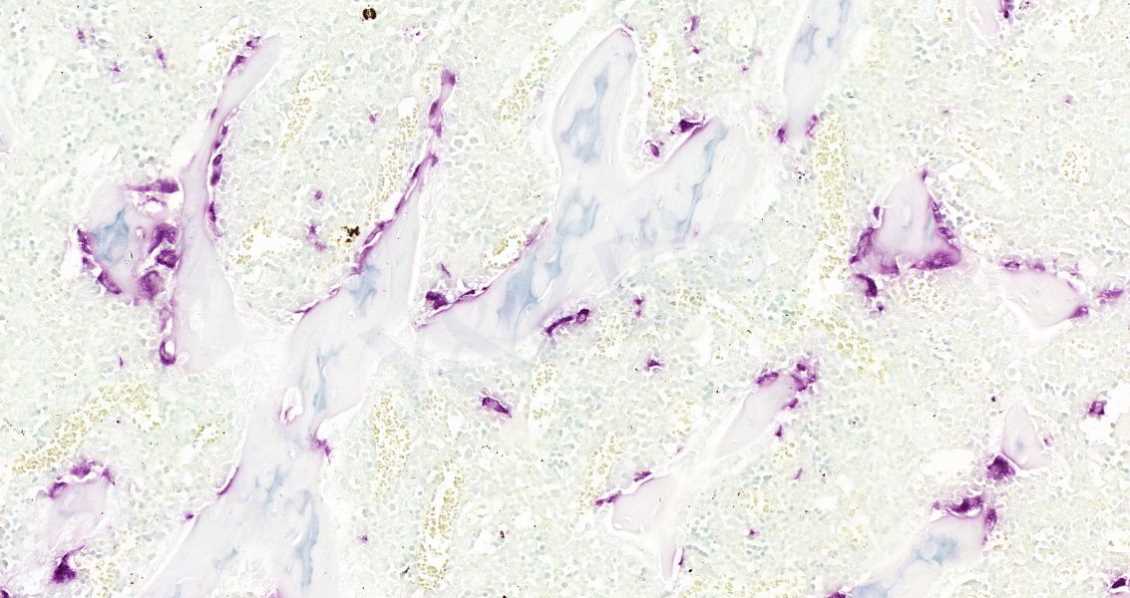

1.HE染色

HE染色是组织学中基础、使用广泛的染色手段,相信大家对此都不陌生。HE染色可以区分一般的骨组织结构和细胞,但单一的HE染色并不能区分新生骨组织的数量、胶原以及其他细胞状态,大多数都需要配合其他染色技术共同观察骨愈合状态。特别的,现在都需要对新生组织进行量化研究,HE染色显然是不能满足要求的。